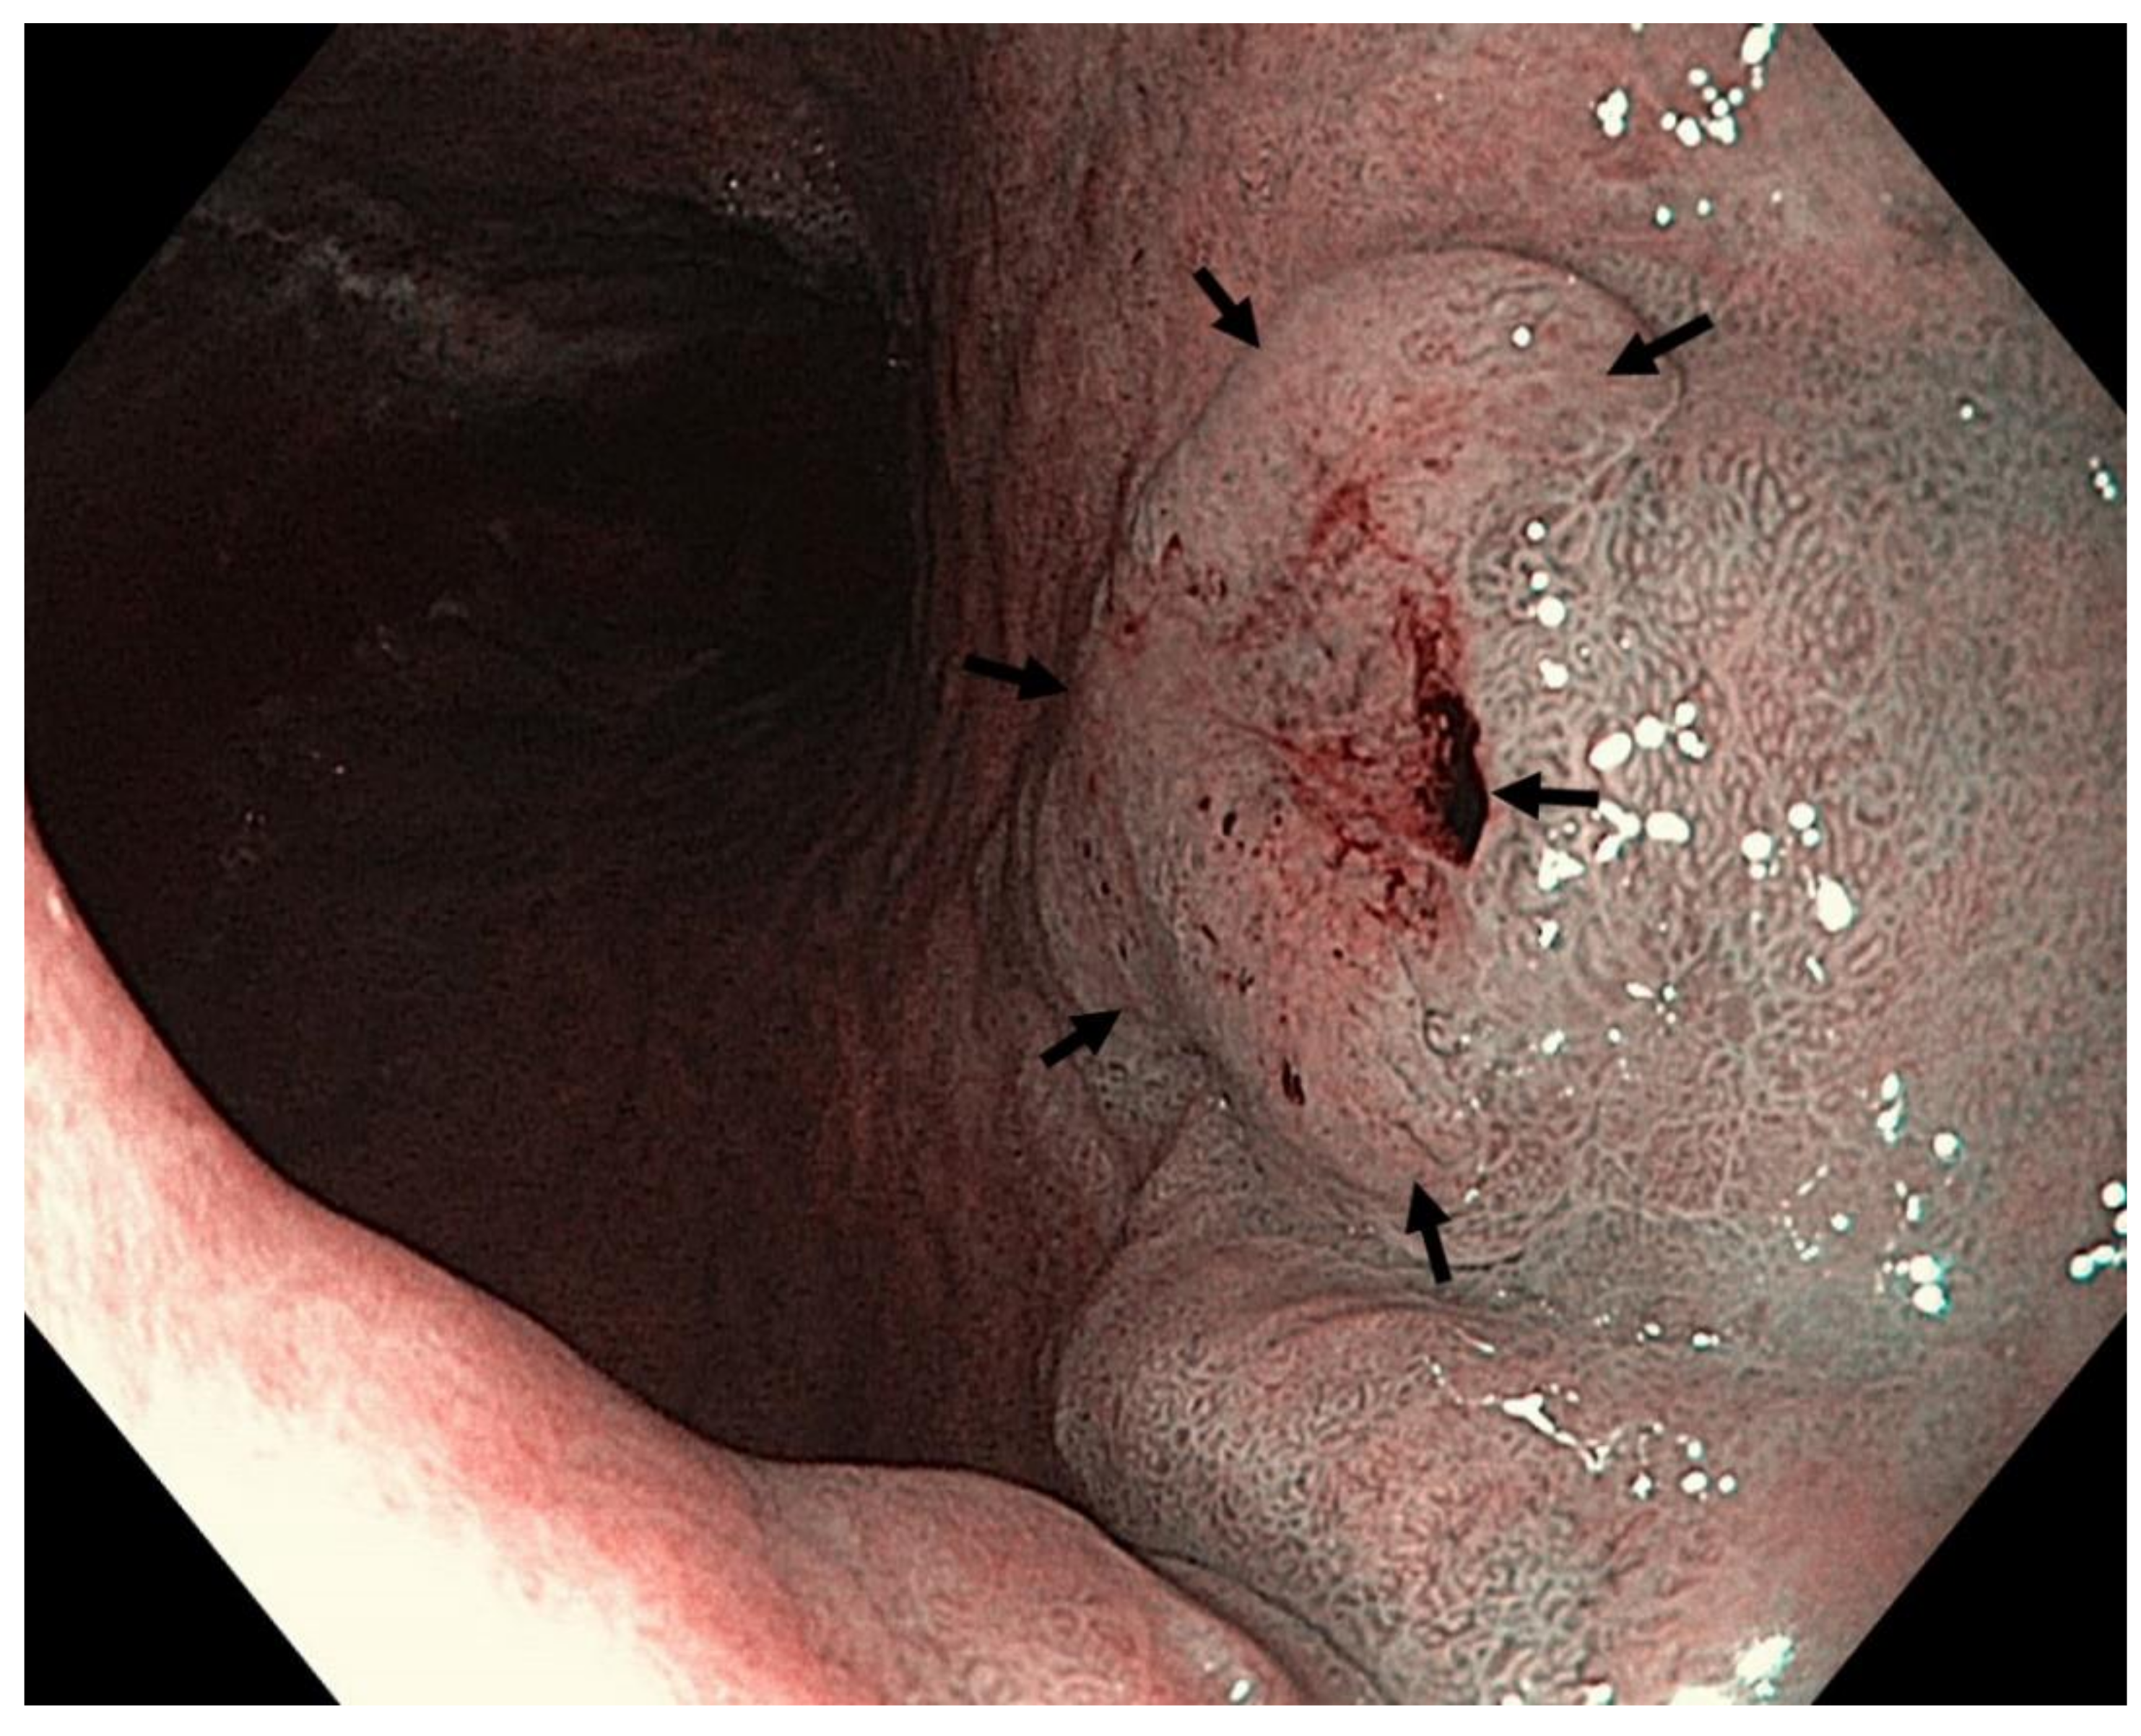

Four features indicative of gastric corporal atrophy have been reported: pallor, loss of gastric folds, prominence of vessels and atrophic border [113,147], Figure 3 and Figure 4.

Grey-white mildly elevated plaques which are surrounded by patchy pink and pale areas are the typical appearance of intestinal metaplasia, Figure 5 and Figure 6. Standard endoscopy alone is not reliable for the diagnosis of intestinal metaplasia. Using image-enhanced and magnification endoscopy, intestinal metaplasia can be recognized in the gastric body by a “groove-type pattern”, which is similar to that observed in the antrum due to the oblique structure of the glands, and is easy to differentiate from the normal straight glands. Intestinal metaplasia in the antrum however is difficult to characterise, as the pre-existing oblique glands are not dissimilar to the “grooved” glands of intestinalisation. The “light blue crest” and “marginal turbid band” (see below) are helpful features to distinguish gastric intestinal metaplasia from the normal antral mucosa, Figure 7 [113].